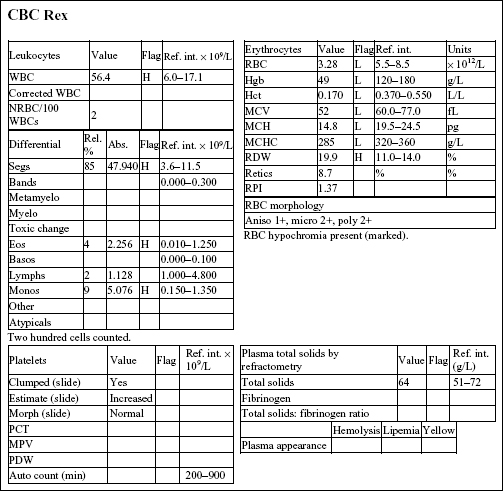

REX, a 14-year-old M(c) German Wirehair Pointer dog, had lethargy, diarrhea (possibly with melena), and pale mucous membranes.

There is a moderate to severe anemia that is microcytic (low MCV and microcytosis on RBC morphology), hypochromic (low MCH and MCHC, and hypochromia noted on RBC morphology), and regenerative (increased reticulocytes and RPI, and 2+ polychromasia on smear examination). The leukogram changes include a moderate to marked neutrophilia, moderate monocytosis, and mild to moderate eosinophilia. Platelet numbers are increased. The erythrogram findings suggest iron deficiency anemia. The leukogram findings suggest chronic inflammation; eosinophilia may be due to concurrent eosinophilic inflammation, allergic disease, parasitic disease, mast cell neoplasia, or a paraneoplastic mechanism (seen most commonly with lymphoid neoplasms). Thrombocytosis may accompany iron deficiency, although the mechanism is not understood; platelets may also be involved in inflammatory processes.

• Rex had an intestinal leiomyosarcoma that had resulted in mucosal ulceration in the duodenum, chronic blood loss, and iron deficiency. The inflammatory leukogram is probably also related to the focus of ulceration, as no other explanation could be found for these changes. Iron deficiency anemia in older dogs is usually caused by intestinal ulceration from chronic nonsteroidal anti-inflammatory drug administration or by intestinal neoplasia. Careful history taking and ancillary testing, such as imaging studies, should help differentiate the two.